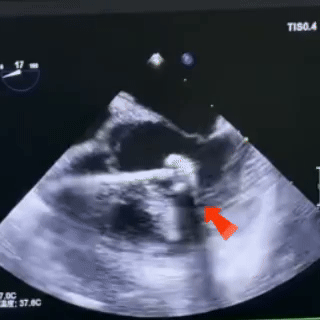

锁定

固定钢缆,轻推鞘管

牵拉成型线,锁定封堵器